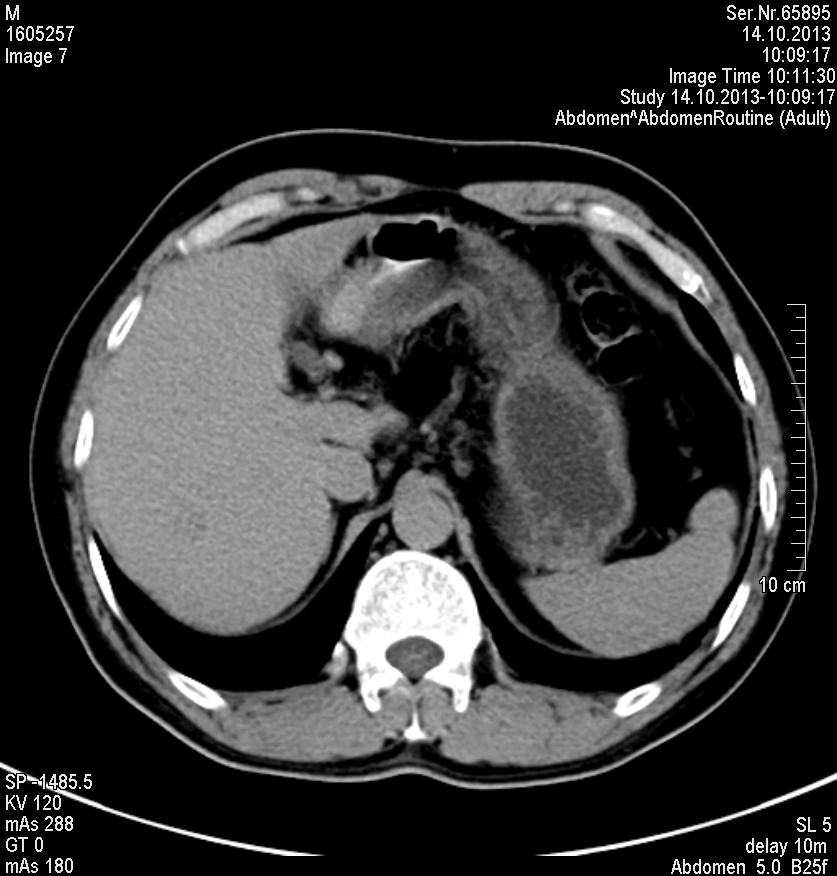

水成像高信号,同反相位均呈低信号,动脉早期轻度强化,其余时期强化不明显

肝脏右叶内有一明显圆形肿块,增强CT肝实质期不强化,MRI水成像高信号,其他呈低信号,动脉早期轻度强化。

考虑肝血管瘤比较多吧!

感觉像小肝癌,强化方式快进快出